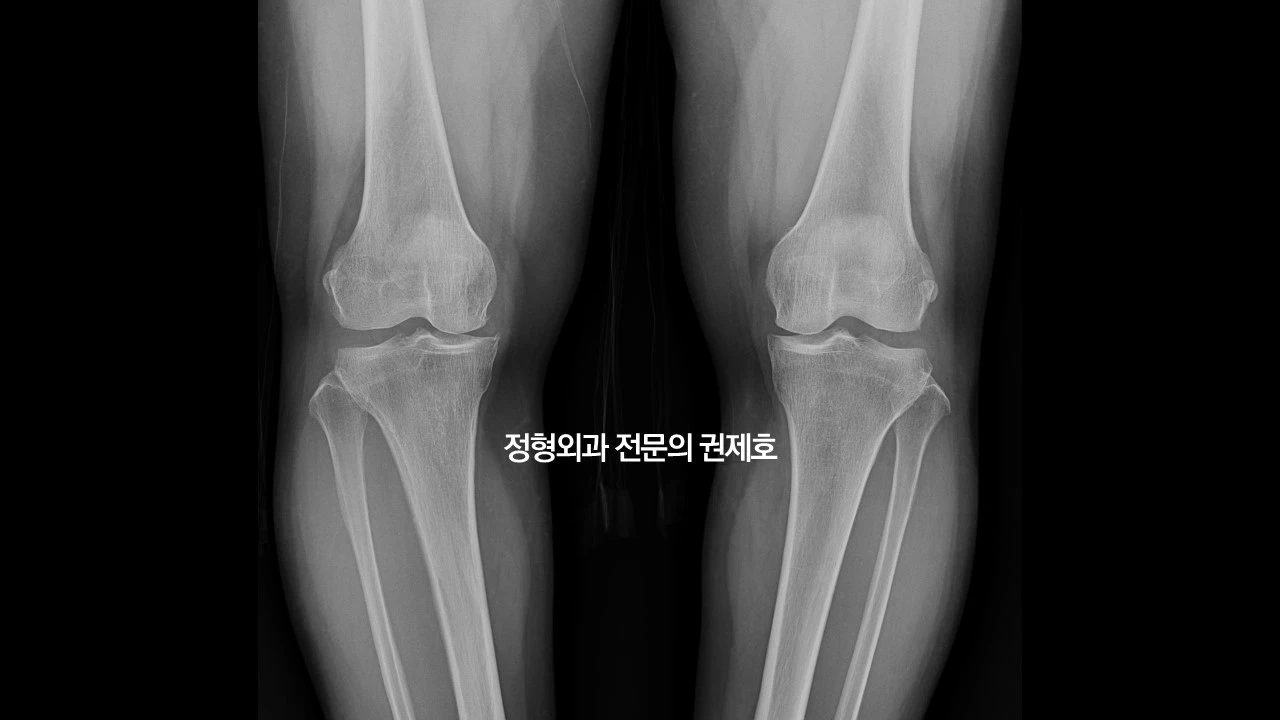

무릎이 아파서 병원에 와보신 분들은 아시겠지만, 보통 여러 장의 사진을 찍지만 중요한 사지만 추렸습니다. 맨 위 사진은 서서 앞에서 촬영한 것이고 그다음 사진은 뒤에서 구부린 상태로 촬영한 로젠버그 사진입니다. 둘 다 보면 관절염이 아주 심해 보이진 않지만, 관절 간격이 좁아진 것이 관찰되고 있습니다.

제가 가장 중요하게 여기는 하지 정렬 검사 사진입니다. 보시면 무릎이 많이 휘어 있는 것을 아실 수 있습니다. 바로 오다리입니다. 아마도 어릴 적부터 원래 오다리였다고 사료되며, 관절염으로 진단받고 관리는 하였으나 아마도 기존에 있던 휜다리가 증상 악화의 요인이 아닐까 생각하며, 비교적 젊은 나이이고, 다른 이상 소견이 있는지 확인하기 위해 MRI 검사를 진행했습니다.